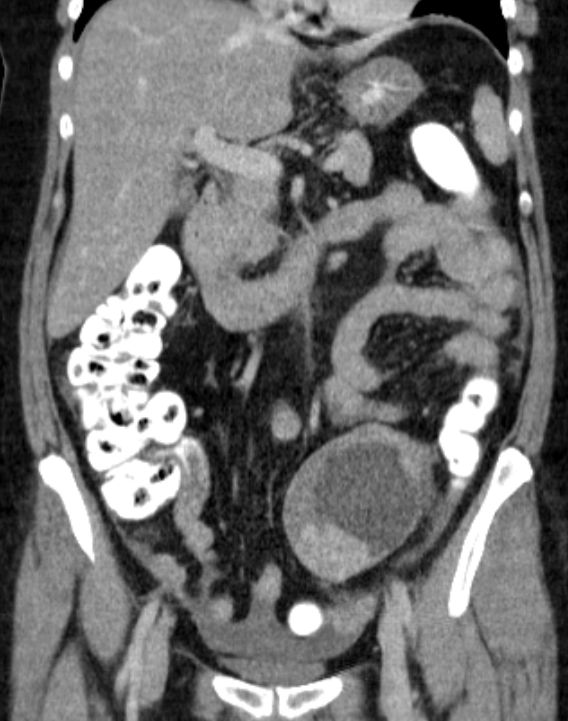

malignes Teratom 58-jährige Frau mit einen malignen Teratom mit Abszedierung und akuter Peritonitis.

Tumormarker AFP 2,86; CEA 2,27; CA 19.9 = 33 060 (N < 37!)

Makroskopie: Mehrteilige, maximal 10,9 cm messende, knotige, gelblichbräunliche und z. T. bröckelig zerfallende Gewebeproben.